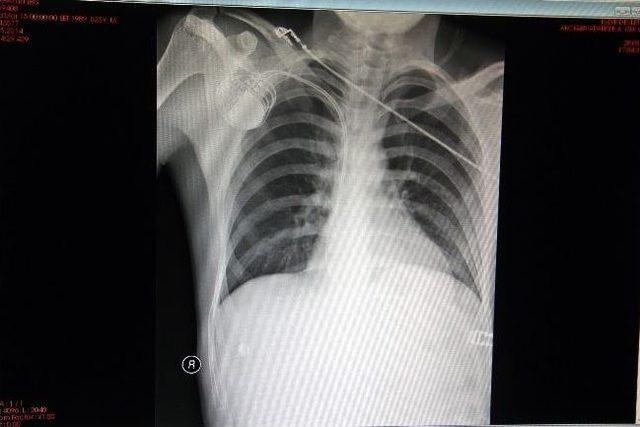

Iğdır Devlet Hastanesi’nde görev yapan uzman Dr. Abdullah Çirit tarafından ilk defa kalp yetmezliği olan genç bir hastaya ‘2 odacıklı kalıcı kalp pili’ takıldı.Iğdır Devlet Hastanesi’nde son beş ay içerinde 11 hastaya ‘kalıcı kalp pili’ takılırken, ilk kez kalp yetmezliği olan Sabahattin Koç (25) isimli hastaya ‘2 odacıklı kalıcı kalp pili’ takıldı.Kardiyoloji uzmanı Dr. Abdullah Çirit, kalp yetmezliği olan hastalarından ani ölümleri önlemek amacıyla son 5 ay içerisinde Iğdır’da 11 hastaya ‘kalıcı kalp pili’ taktıklarını belirtti. Iğdır’da ilk kez genç bir hastaya ‘2 odacıklı kalıcı kalp pili’ takma operasyonu yaptıklarını ifade eden Çirit, “Bize gelen hastamızın ciddi anlamda halsizlik sorunu vardı. Hastamıza kalıcı kalp pili taktıktan sonra sendromları tamamen geriledi ve hastamız şifa buldu” dedi.“ÜÇÜNCÜ BASAMAK HASTANEDE YAPILAN İŞLEM BURADA DA YAPILDI”Üçüncü basamak hastanede yapılan işlemin burada yapılmasının çok sevindirici olduğunu ifade eden Iğdır Devlet Hastanesi Yöneticisi Op. Dr. Abdulhamit Bozyiğit ise, “Bu ve benzeri operasyonları rutin hale getireceğiz. Bu sayede Iğdır’daki hastalarımız 300-400 kilometre uzaklıkta sağlık kuruluşlarına gitmek zorunda kalmayacaklardır. Türkiye’nin en doğusu Iğdır’da sağlık anlamında her türlü zor cerrahi operasyonları yapmayı planlamaktayız” diye konuştu.Yapılan operasyonla sağlığını çok iyi olduğunu ifade eden hasta Sabahattin Koç da, “Daha önce Erzurum’da tedavi gördüm ve orada bana anjiyo yapıldı. Üzerimde halsizlik vardı. Burada hocam beni muayene etti. Burada bana pil takabileceğini söyledi. Ben de hocama çok güvendiğim için tamam dedim ve şimdi sağlığım çok iyi” şeklinde konuştu.